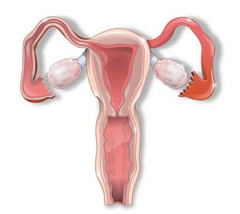

УЗИ матки и придатков – ультразвуковое обследование, дающее представление врачу-гинекологу о состоянии матки и придатков (мат...

Гинекология в буквальном переводе означает «наука о женщине». Это область медицины, занимающаяся проблемами женской половой сис...